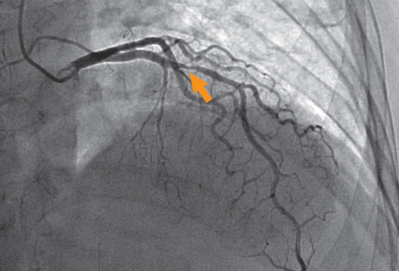

来院時の心電図は完全右脚ブロックで以前と変化はなかった。トレッドミル負荷心電図検査では目標心拍数に達したが、十分な判定ができる所見は得られなかった。冠動脈造影検査で、左前下行枝に50~75%程度の狭窄病変を認めた。矢印は病変部を示す。血行再建術の適応と考えられた。